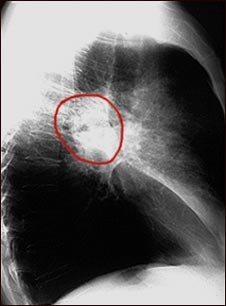

Cáncer de pulmón- Radiografía lateral del tórax

Vista lateral de una radiografía de tórax de un paciente con cáncer en la parte central del pulmón.